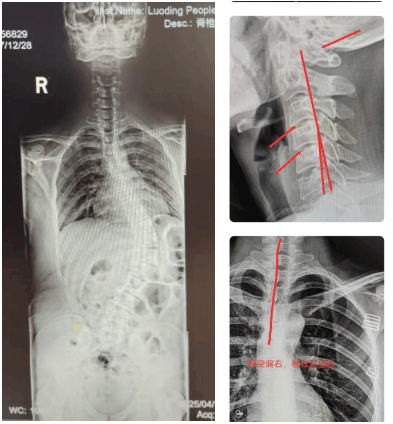

青少年脊柱側(cè)彎、頸椎反弓